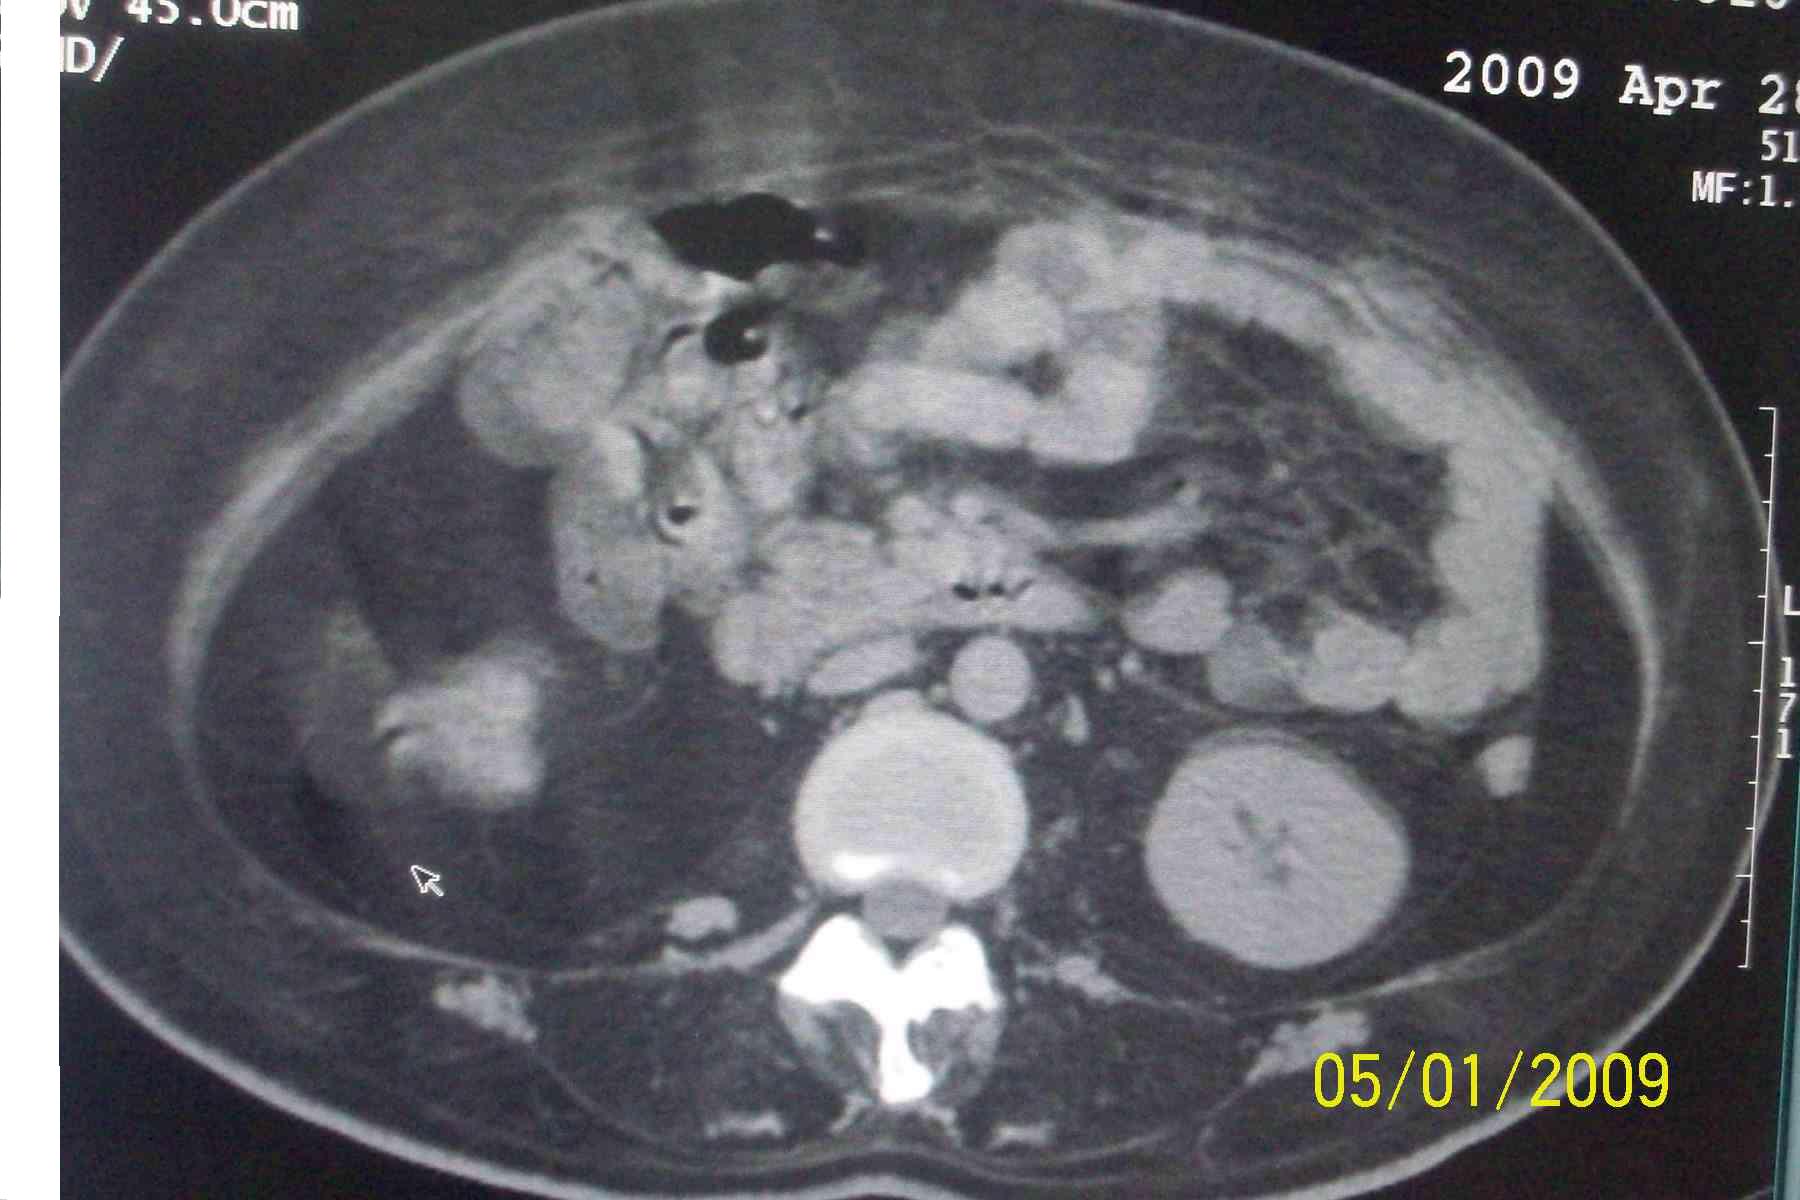

以下是引用杀毒软件在2009-5-1 17:43:00的发言:[br]良性对称性脂肪增多症

以下是引用ncy888888在2009-5-1 17:39:00的发言:[br]肾怎么弄丢了一个。